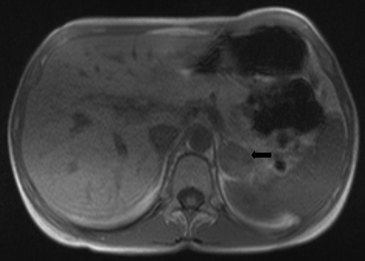

Los valores más utilizados son un 40% de lavado relativo de en fase tardía realizada a los 15 minutos y un lavado absoluto de 60%. De este modo cualquier lesión que muestre un lavado relativo mayor al 40% o absoluto mayor al 60% es consistente con un adenoma, con una sensibilidad y especificidad cercana al 100% (Figura 14 a, b y c). Dado la rapidez con que se obtiene un TAC de abdomen en la actualidad, algunos trabajos han recomendado utilizar cortes tardíos realizados a los 10 minutos, con el fin de optimizar el tiempo de examen, y utilizar un valor relativo de corte más conservador del 50%9.

A

B

C Figura 14. Tomografía computada de un adenoma suprarrenal izquierdo típico. Se ha colocado un circulo que representa la región de interés en la lesión de la glándula suprarrenal izquierda, obteniendo una medición promedio (Avg) expresada en unidades Hounsfield (UH). En fase precontraste (a) su densidad es de 0 UH, (flecha), en fase protovenosa (b) alcanza una densidad de 59 UH (cabeza de flecha), y en fase tardía (c) su lavado es de aproximadamente un 50%, llegando a una densidad de 30 UH.